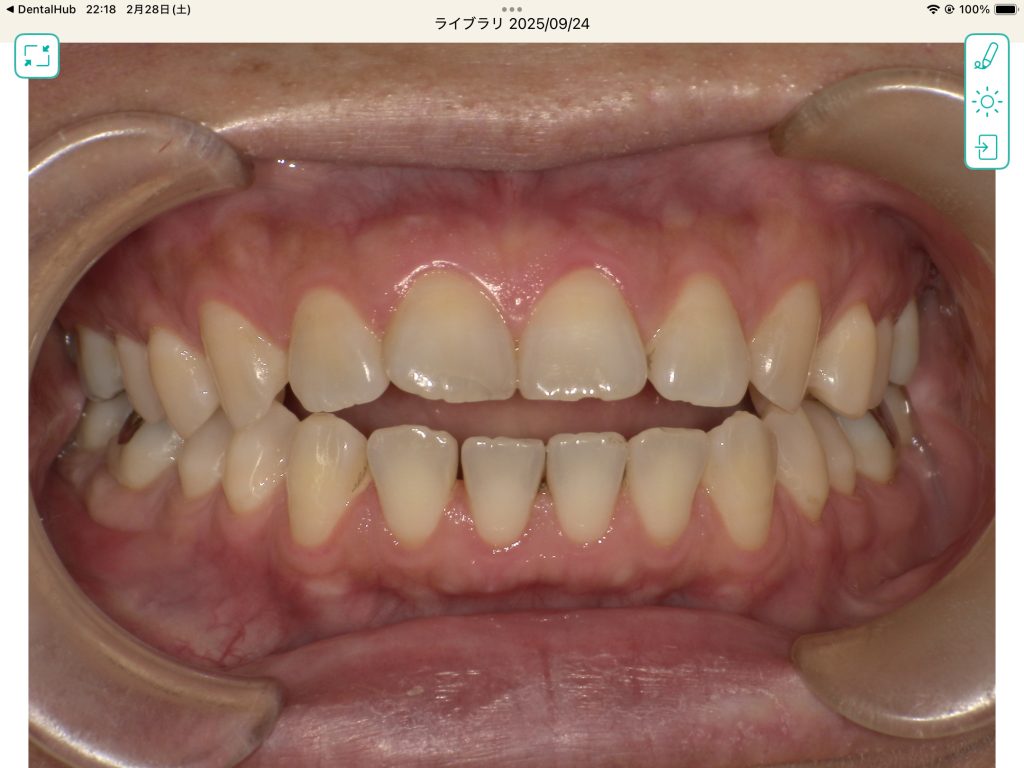

主訴 開咬をなおしたい

治療開始

まだ矯正途中ですが、2ヶ月で開咬を改善出来ました。(矯正担当は村本先生)